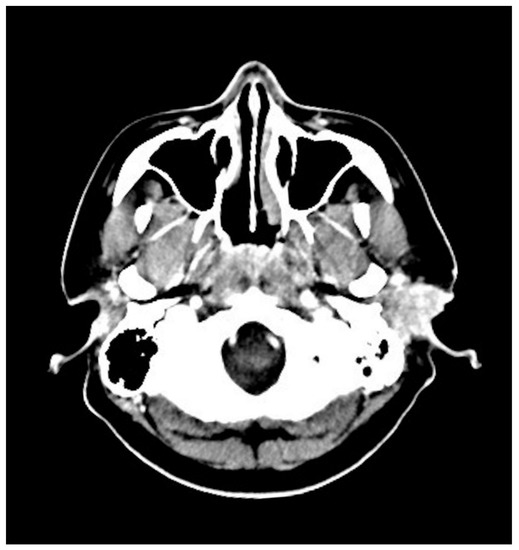

| Gomaa et al., 2010 | Female | 47 | Otalgia, EAC swelling | No osseous erosion | Radio-uptake | CD4, CD5, CD30 | NA | RT |

| Marcal et al., 2012 | Female | 68 | Otalgia, hypoacusis | No osseous erosion | NA | CD3, CD5, CD30 | Negative | RT |

| Present case, 2021 | Male | 34 | Painless mass | No osseous erosion | Radio-uptake | CD3, CD30 | Positive | CCRT |